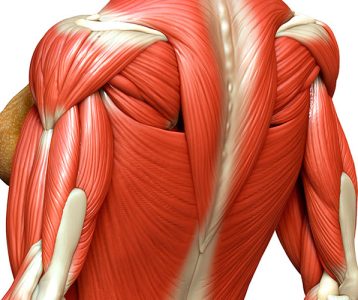

A língua é um órgão muscular vital no corpo humano, que desempenha papel fundamental em funções como deglutição, paladar e fala. Além disso, sua forma e aparência podem fornecer pistas valiosas sobre a saúde geral. Alterações em cor, tamanho e textura da língua, assim como a presença de lesões locais, podem denunciar problemas com a higiene e condições clínicas específicas que demandam cuidado médico ou odontológico imediato.